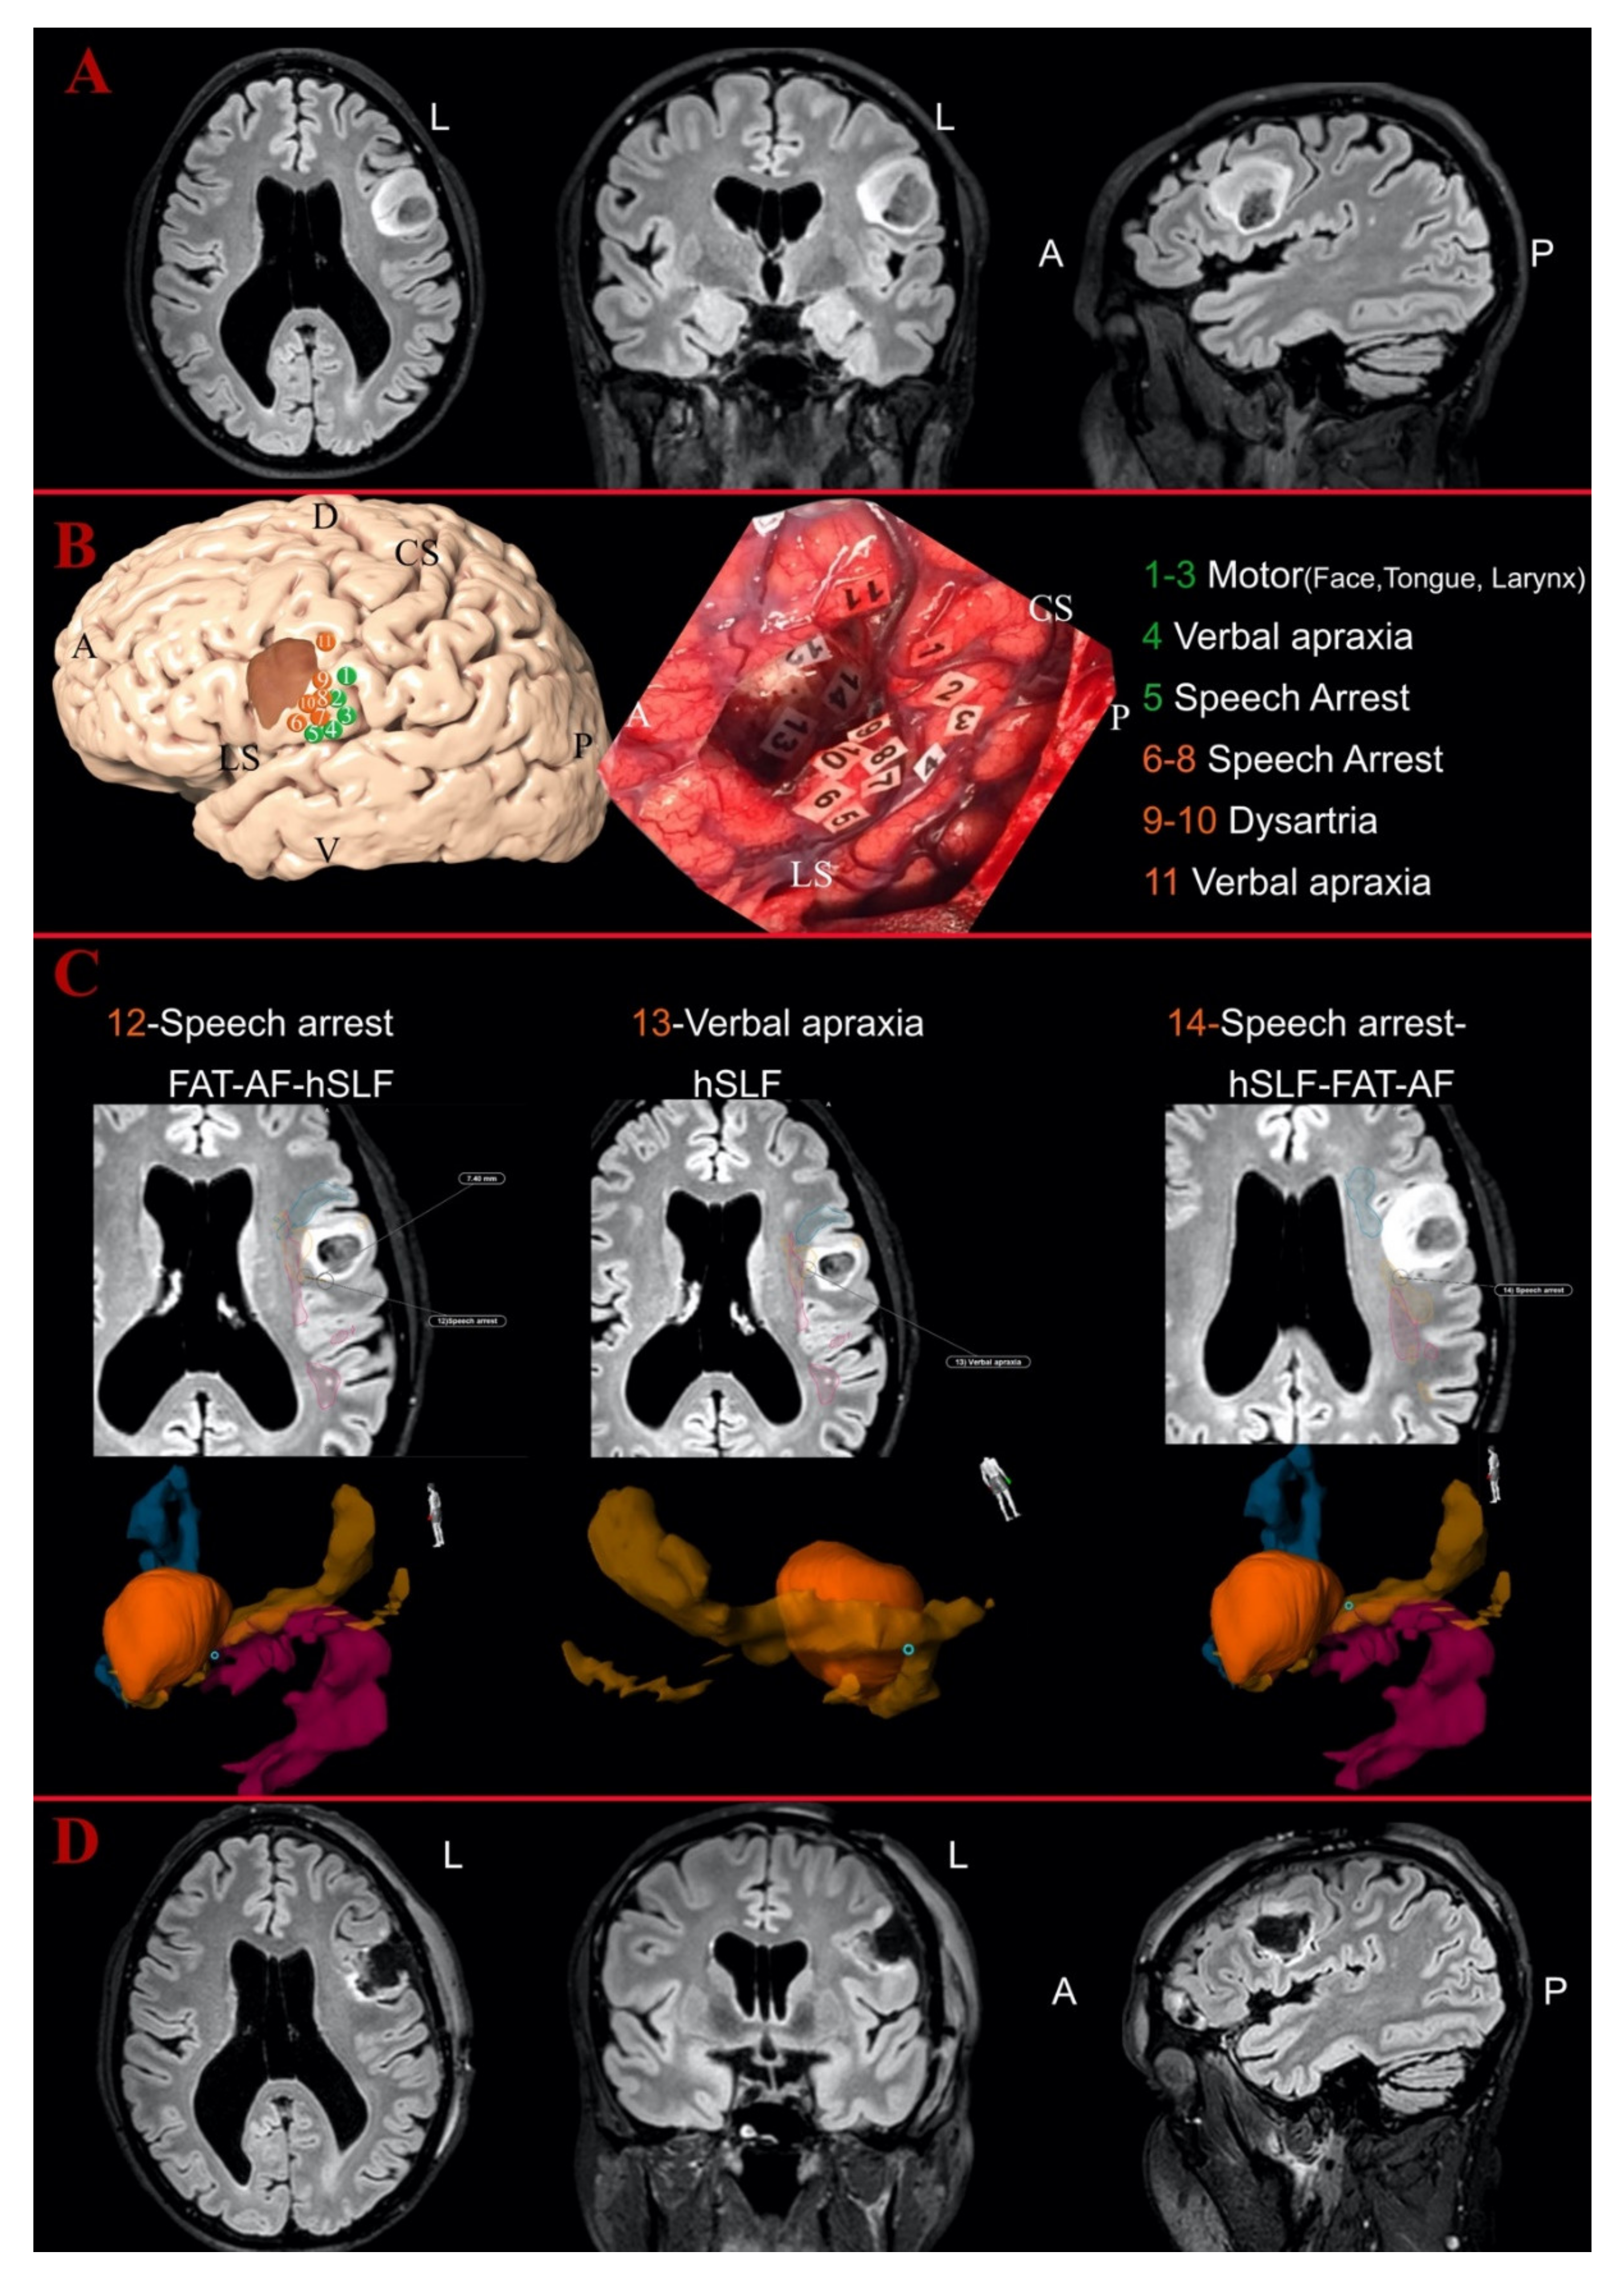

2.5. Surgical and Stimulation Technique

2.6. Postoperative Analysis of Eloquent Points

3.3. Intraoperative Findings

3.4. Postoperative Analysis